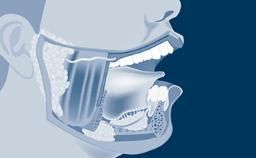

Introduction to Implant Dentistry

Anatomy with Relevance to Implant Surgery

Learning Module